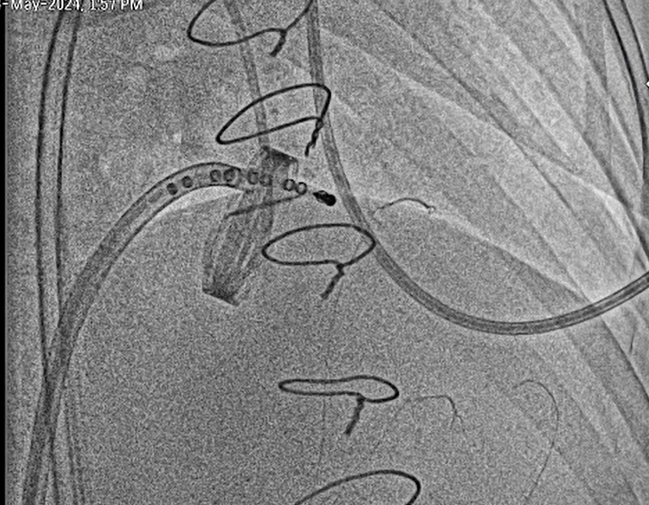

Bilateral Radial and Femoral artery access taken along with Right Femoral vein under Ultrasound guidanceCarotid filter was placed in Right carotid artery through Right femoral arteryTwo Peripheral balloons were kept in left common carotid and left subclavian through left femoral and radial artery routeTranseptal puncture through right femoral vein was done and was later exchanged with 8.5fr deflectable Agilis sheathThrough Agilis sheath valve orifices was crossed with 0.032 Terumo wireUpper Orifice was dilated with 12x140mm peripheral balloonCentral Orifice was dilated with 5x60mm peripheral balloonLower Orifice was dilated with 10x140mm peripheral balloonPost Procedure Good movement of both leaflets , still upper leaflet movement was not satisfactory.6fr Decapolar mapping catheter was used for pecking the upper leaflet and later again it was dilated with 12x140mm peripheral balloon.Movement of both leaflets were good

Percutaneous Management of Stuck Prosthetic leaflets can be done as a Bail-out options in such clinical scenarios where Redo-surgery is not a possibility.Post Procedure Immediate hemodynamic improvements can be seenAlways should be done with cerebral protection device-if only one device is available then we can use 2 peripheral balloon in carotid and subclavian artery to prevent cardioembolic stroke.Staged Redo procedures can be done after stabilisation from percutaneous management as it is bridge to Redo Surgical Interventions for Prosthetic Valve